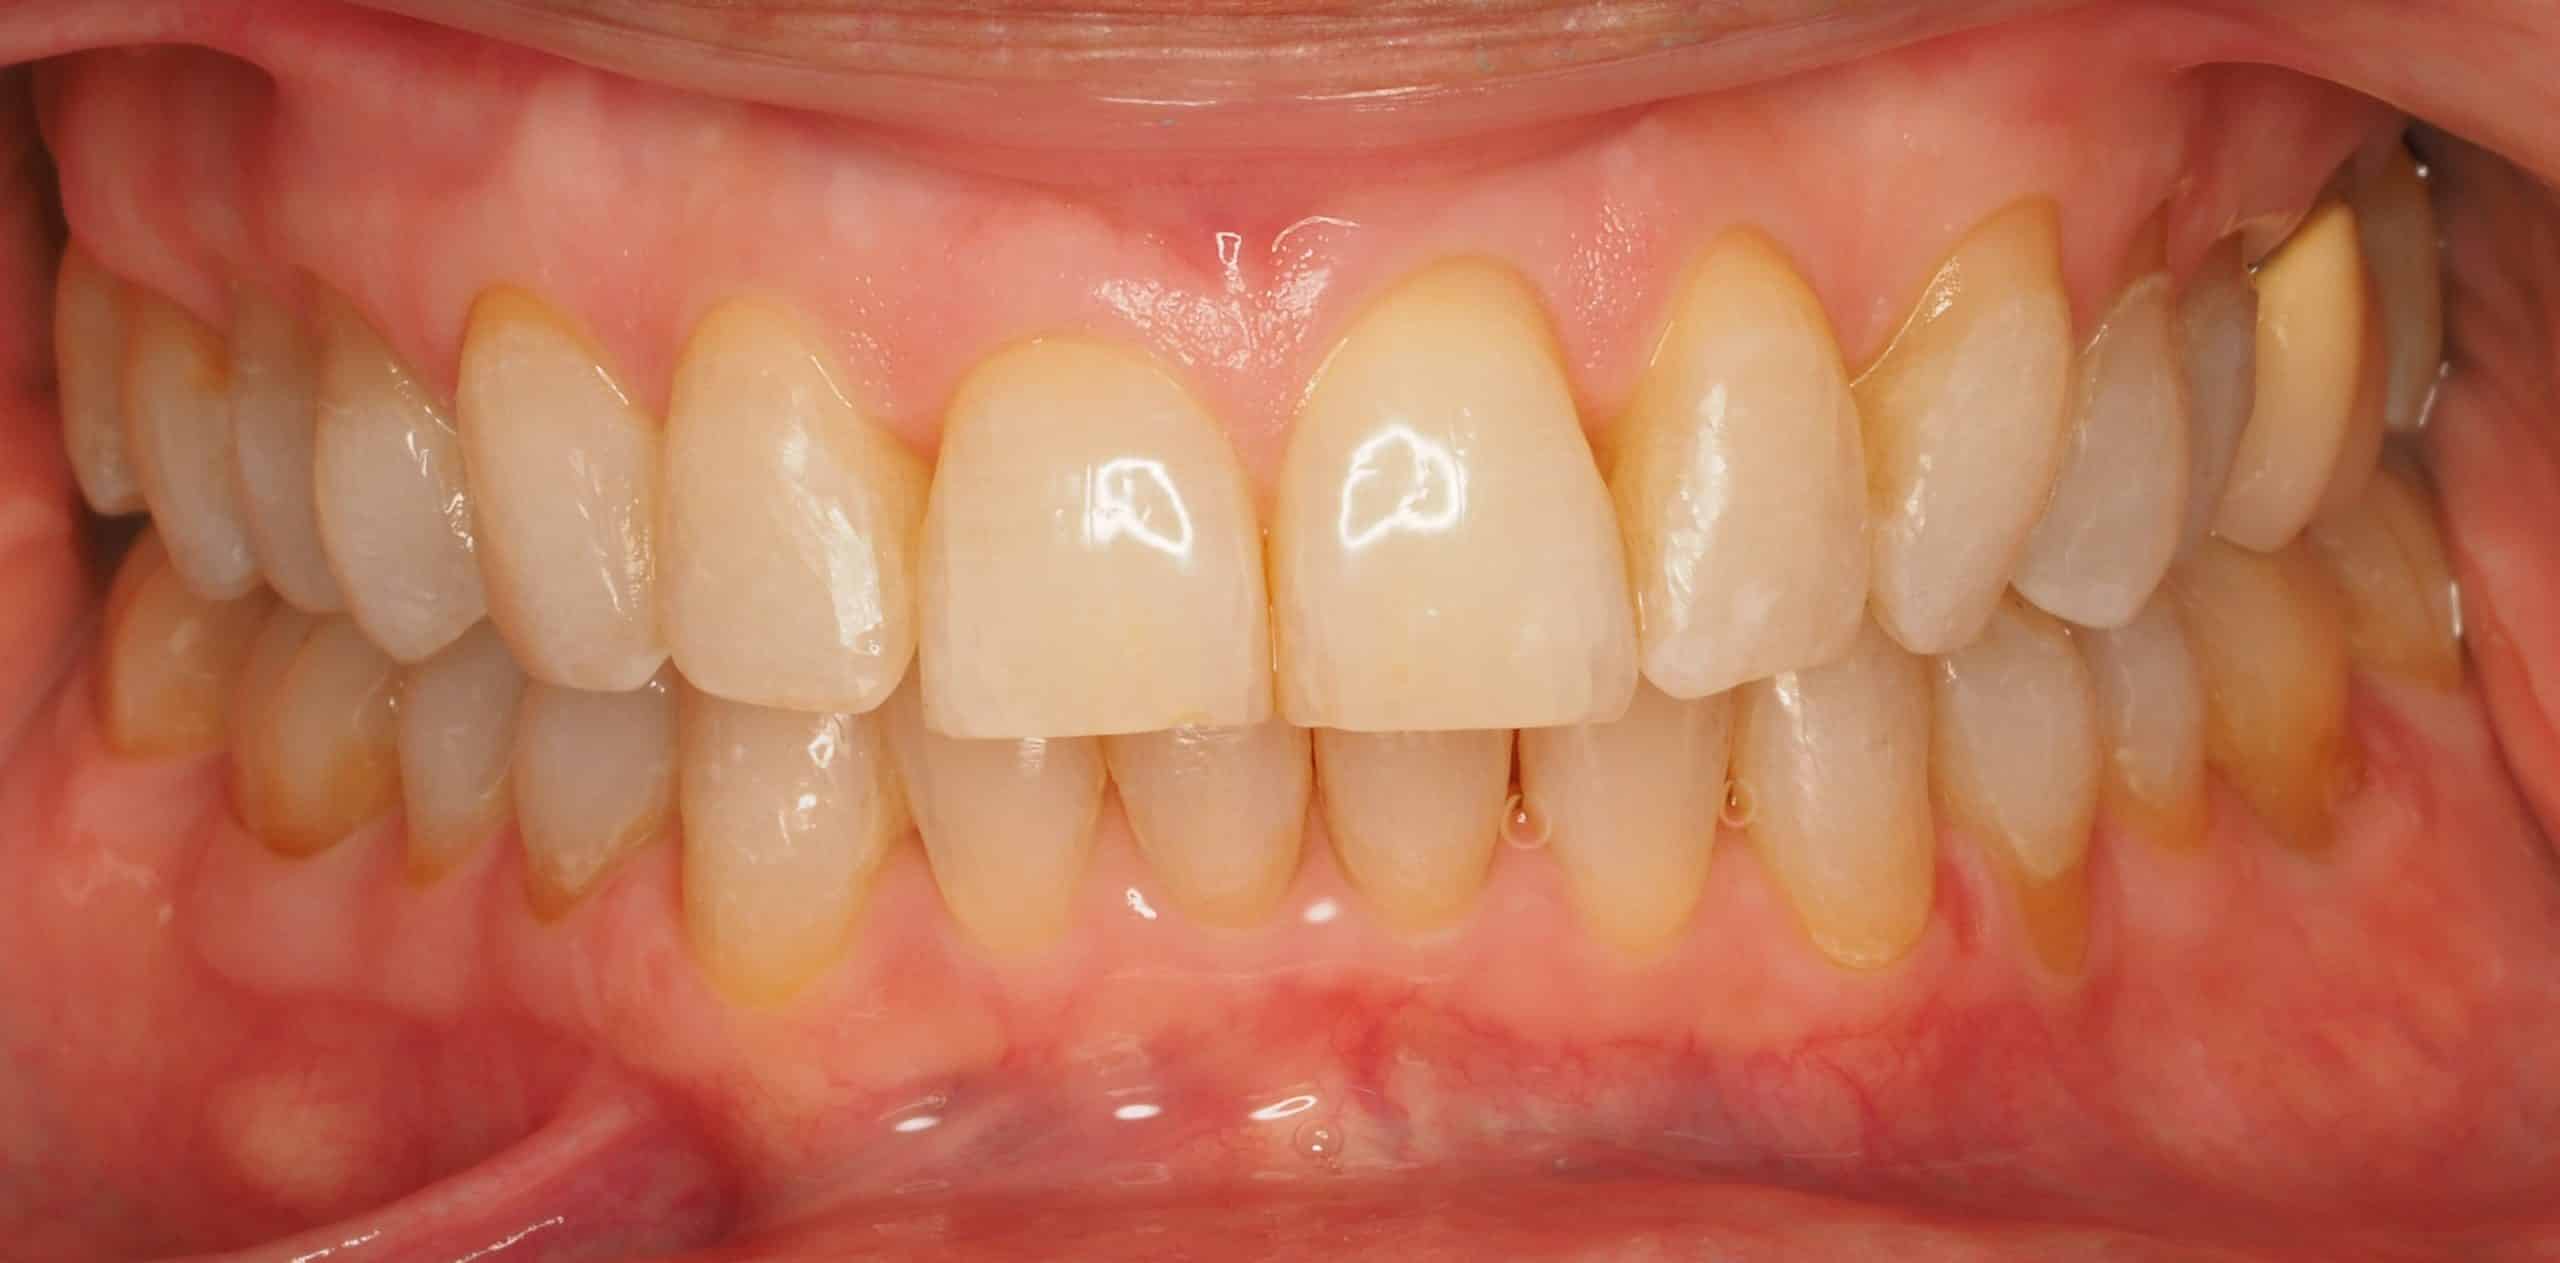

Carillas de cerámica feldespática superiores e inferiores con cierre de diastemas.